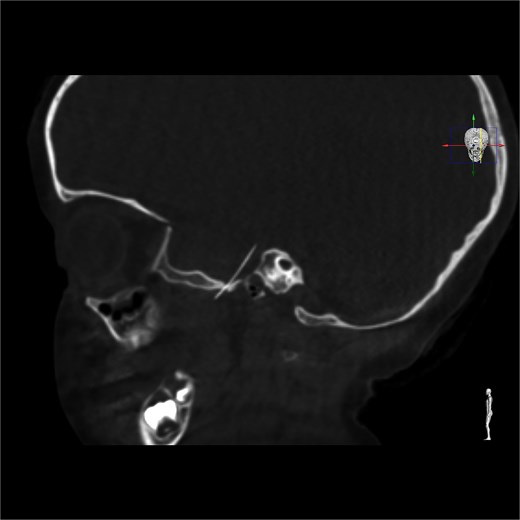

Once in the operating theatre, a CBCT was performed before starting the procedure to assess the precise position of the needle. Surprisingly, the needle had migrated, likely due to masticatory function, and had traversed the foramen ovale into the middle cranial fossa, below the right temporal lobe (Fig. 2). A neurological re-evaluation reported no neurological deficits. Given the new location of the needle, the surgical plan was revised in consultation with neurosurgeons, and the parents provided consent for a neurosurgical approach. It was agreed to perform intraoperative angiography and angio-CT to assess the integrity of the Circle of Willis.

Intracranial CT scan showing the intracranial migration of the needle through the foramen ovale.